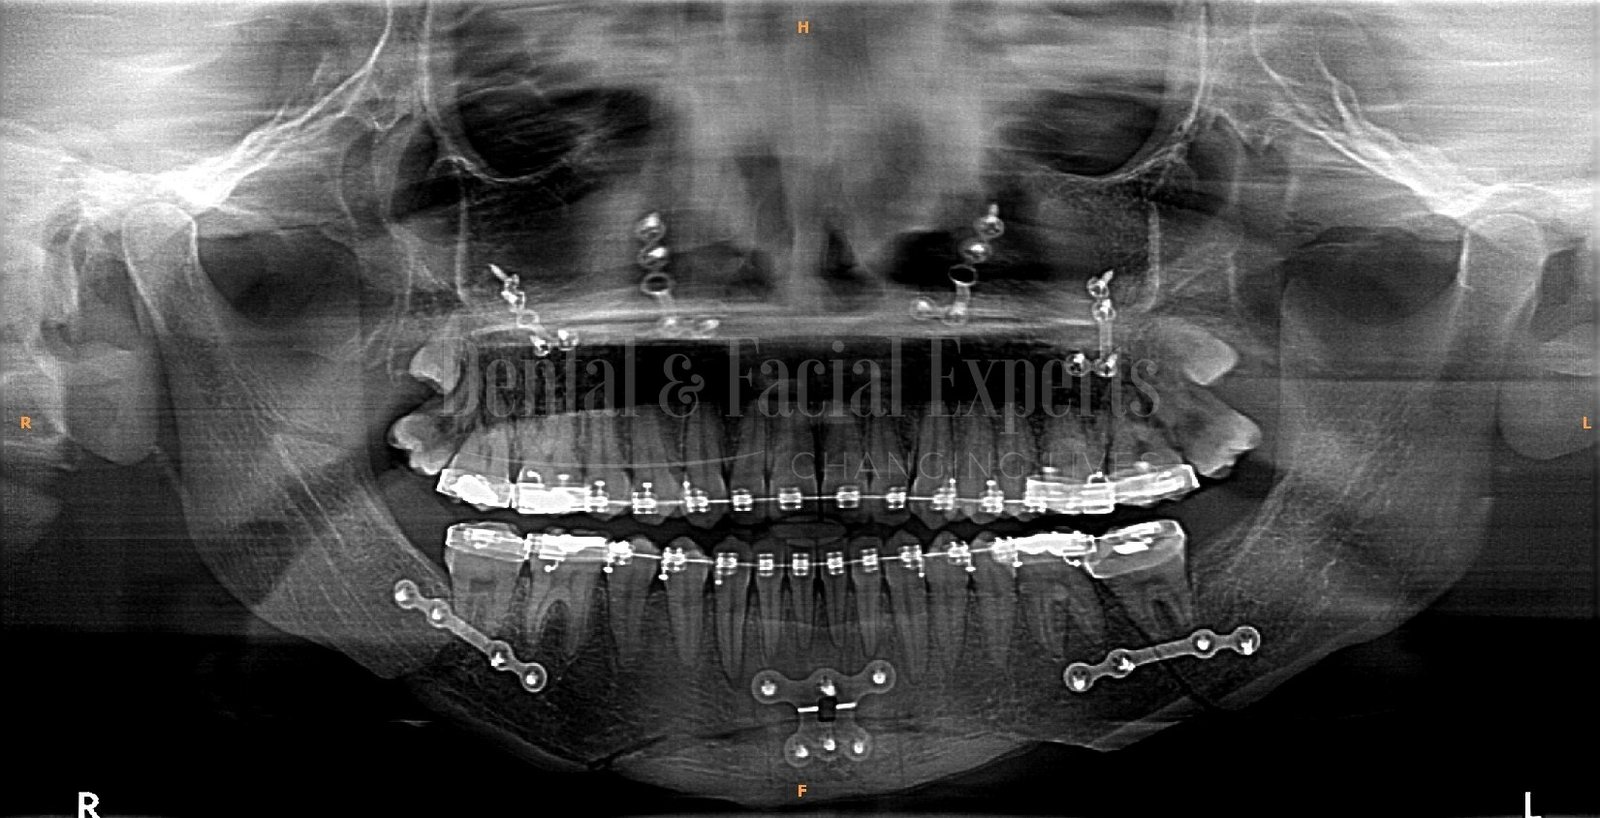

La cirugía maxilofacial es una especialidad médico-quirúrgica que aborda patologías, malformaciones y traumatismos de la cara, mandíbula, maxilares, boca y cuello. Su objetivo es restaurar la funcionalidad y mejorar la estética facial, abarcando procedimientos tanto reconstructivos como cosméticos.